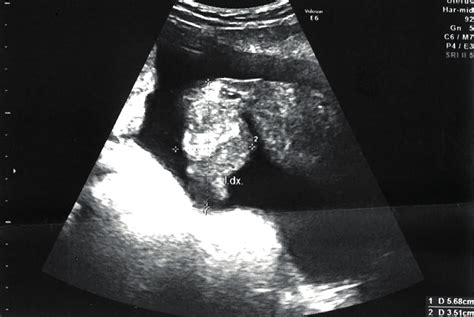

Ultrazvukové vyšetření

Ultrazvuk je jednou z nejběžnějších metod. Již od 12. týdne těhotenství lze s určitou přesností pohlaví odhadnout, ale nejpřesnější je ultrazvukové vyšetření kolem 20. týdne těhotenství (tzv. druhý screening). Lékař dokáže s vysokou pravděpodobností určit pohlaví, pokud je plod ve vhodné poloze a jeho genitálie jsou viditelné.